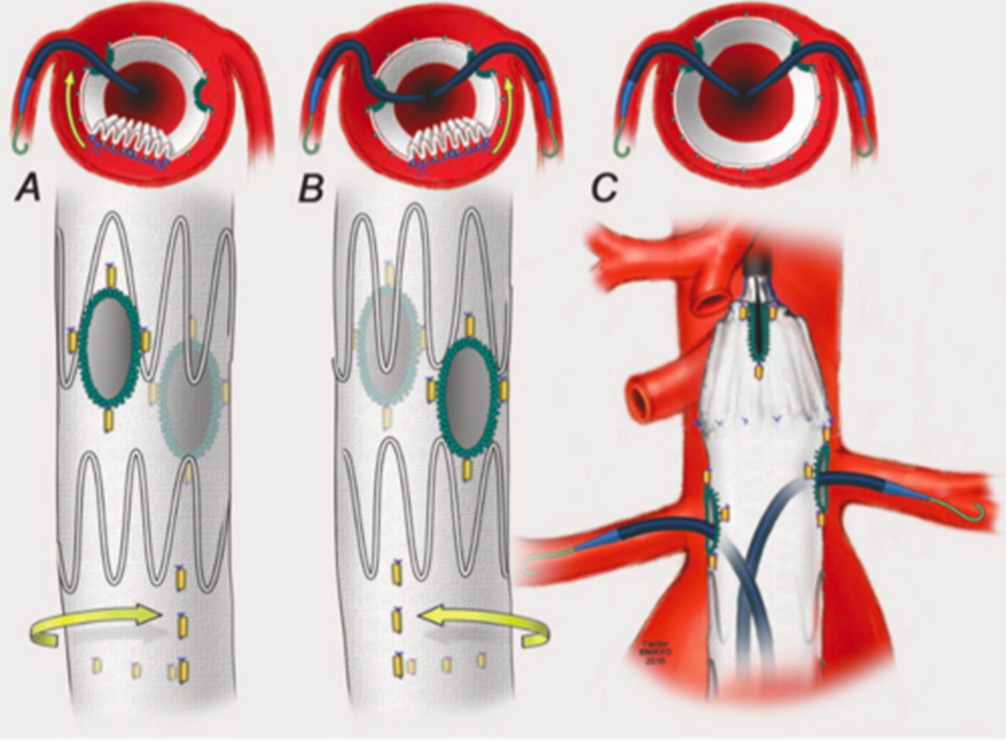

束径技术

束径技术辅助:大支架的对位,旋转调整、留下超选空间,束径方法有多种,预置导丝

合理束径可保证分支动脉有足够的血流灌注;

束径幅度及范围:根据解剖学特征,个性化调整束径大小及长度;

束径钢丝采用V18导丝;

选定合适位置,经支架输送系统外管穿刺导入;

导入点在支架释放前要始终位于血管内,以避免孔洞漏血;